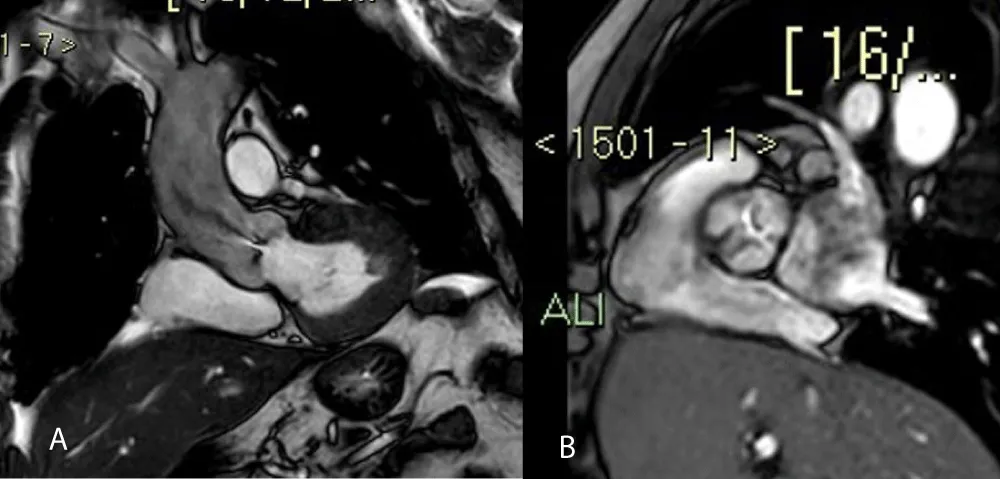

• Cine Steady State Free Precession (SSFP) sequences, ideal for functional cardiac studies (Figure 2)

• Additional SSFP sequences in order to study the aortic valve plane (to study its morphological characteristics and to calculate the AVA) (Figures 3A and 3B)

Download Image

Figure 2: SSFP four chambers, in systolic phase.

Figure 3: Coronal-axial valve aortic planes show a jet of anterograde turbulent flow (3A) and stenotic area (3B).